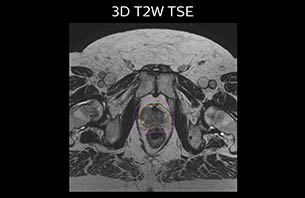

A 77-year-old male with prostate cancer cT3aN0M0, Gleason 8 and PSA 52 μg/L referred to androgen deprivation and radiation therapy with a prescribed dose of 50 Gy to the pelvic lymph node regions and 76 Gy to the prostate.

MR-only simulation workflow The 3D T1W FFE mDIXON sequence provides in-phase, water and fat images in one acquisition. Target and organs-at-risk are delineated on the 3D T2W TSE images. Prostate GTV is shown in orange, PTV in purple. The 3D bFFE sequence is used by the planner to mark the position of the fiducial markers (gold anchors) and contours are transferred to the digitally reconstructed radiographs (DRRs).

Based on the 3D T1W mDIXON images, MR-based density maps (MRCAT) are automatically generated. The VMAT (Volumetric Modulated Arc Therapy) plan is generated in TPS, based on MRCAT as primary image set. During the commissioning phase, dosimetric agreement between MRCAT-based and CT-based dose plans was studied and differences in the PTV dose were found to be minimal (<1% for most patients). Average difference in PTV mean values was 0.8% over the study group (n=62).